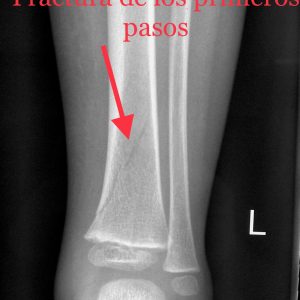

tib-fract-toddler

In